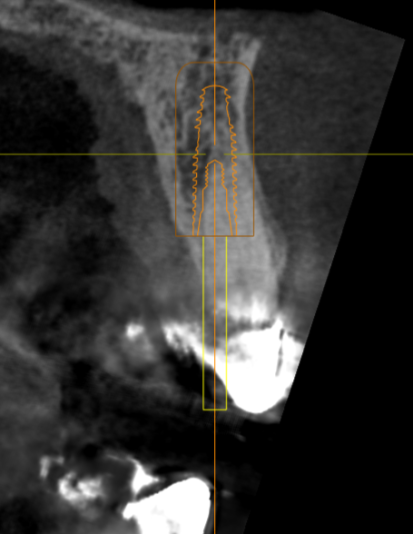

Immediate #7

Thoughts on angulation, depth, F/L position? I feel like its too deep, but wanted to at least be bone level on the lingual. Use his old crown as a temp if I achieve enough torque?

Could tip apical lingually and go cementable

In planned position, the apical third awfully close to the cortical plate.

This is a 3.75 x 13. Will be placing a 3.5 x 13

This is a neodent Helix aqua. Was curious about a 3.3 Roxolid using smile in a box as well. The last time I did this, I lost quite a bit of buccal plate.